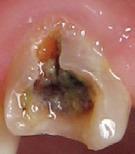

In the endodontic stage, conservative endodontic preparation and obturation with modern techniques are performed as they are for any tooth. All endodontic procedures are performed under an operating microscope to maximize visualization and illumination of the fracture line (Fig 1). The coronal portion of the newly placed gutta percha is removed 2 to 3 mm below the deepest extent of the crack in the affected canal to prepare for intraradicular barrier placement (Fig 2). Gutta percha is also removed 2 to 3 mm into the other noncracked canal orifices in the tooth to prepare for traditional orifice barriers. Microscopic transillumination with a fiber-optic light, in which an LED light probe is placed against buccal or lingual tissues overlying the roots, is utilized to illuminate the root and enhance visualization of the crack (Fig 3). A flowable resin-modified glassionomer or composite resin is then placed in this newly created void from the level of the gutta percha to the floor of the pulp chamber in all canal orifices (Fig 4). A composite resin core is then placed to permanently restore the endodontic access. If a temporary or permanent crown is not placed immediately after the endodontic procedures, the tooth is reduced

Fig 1. Microscopic visualization of the radicular extension of the crack (arrows) entering the canal.